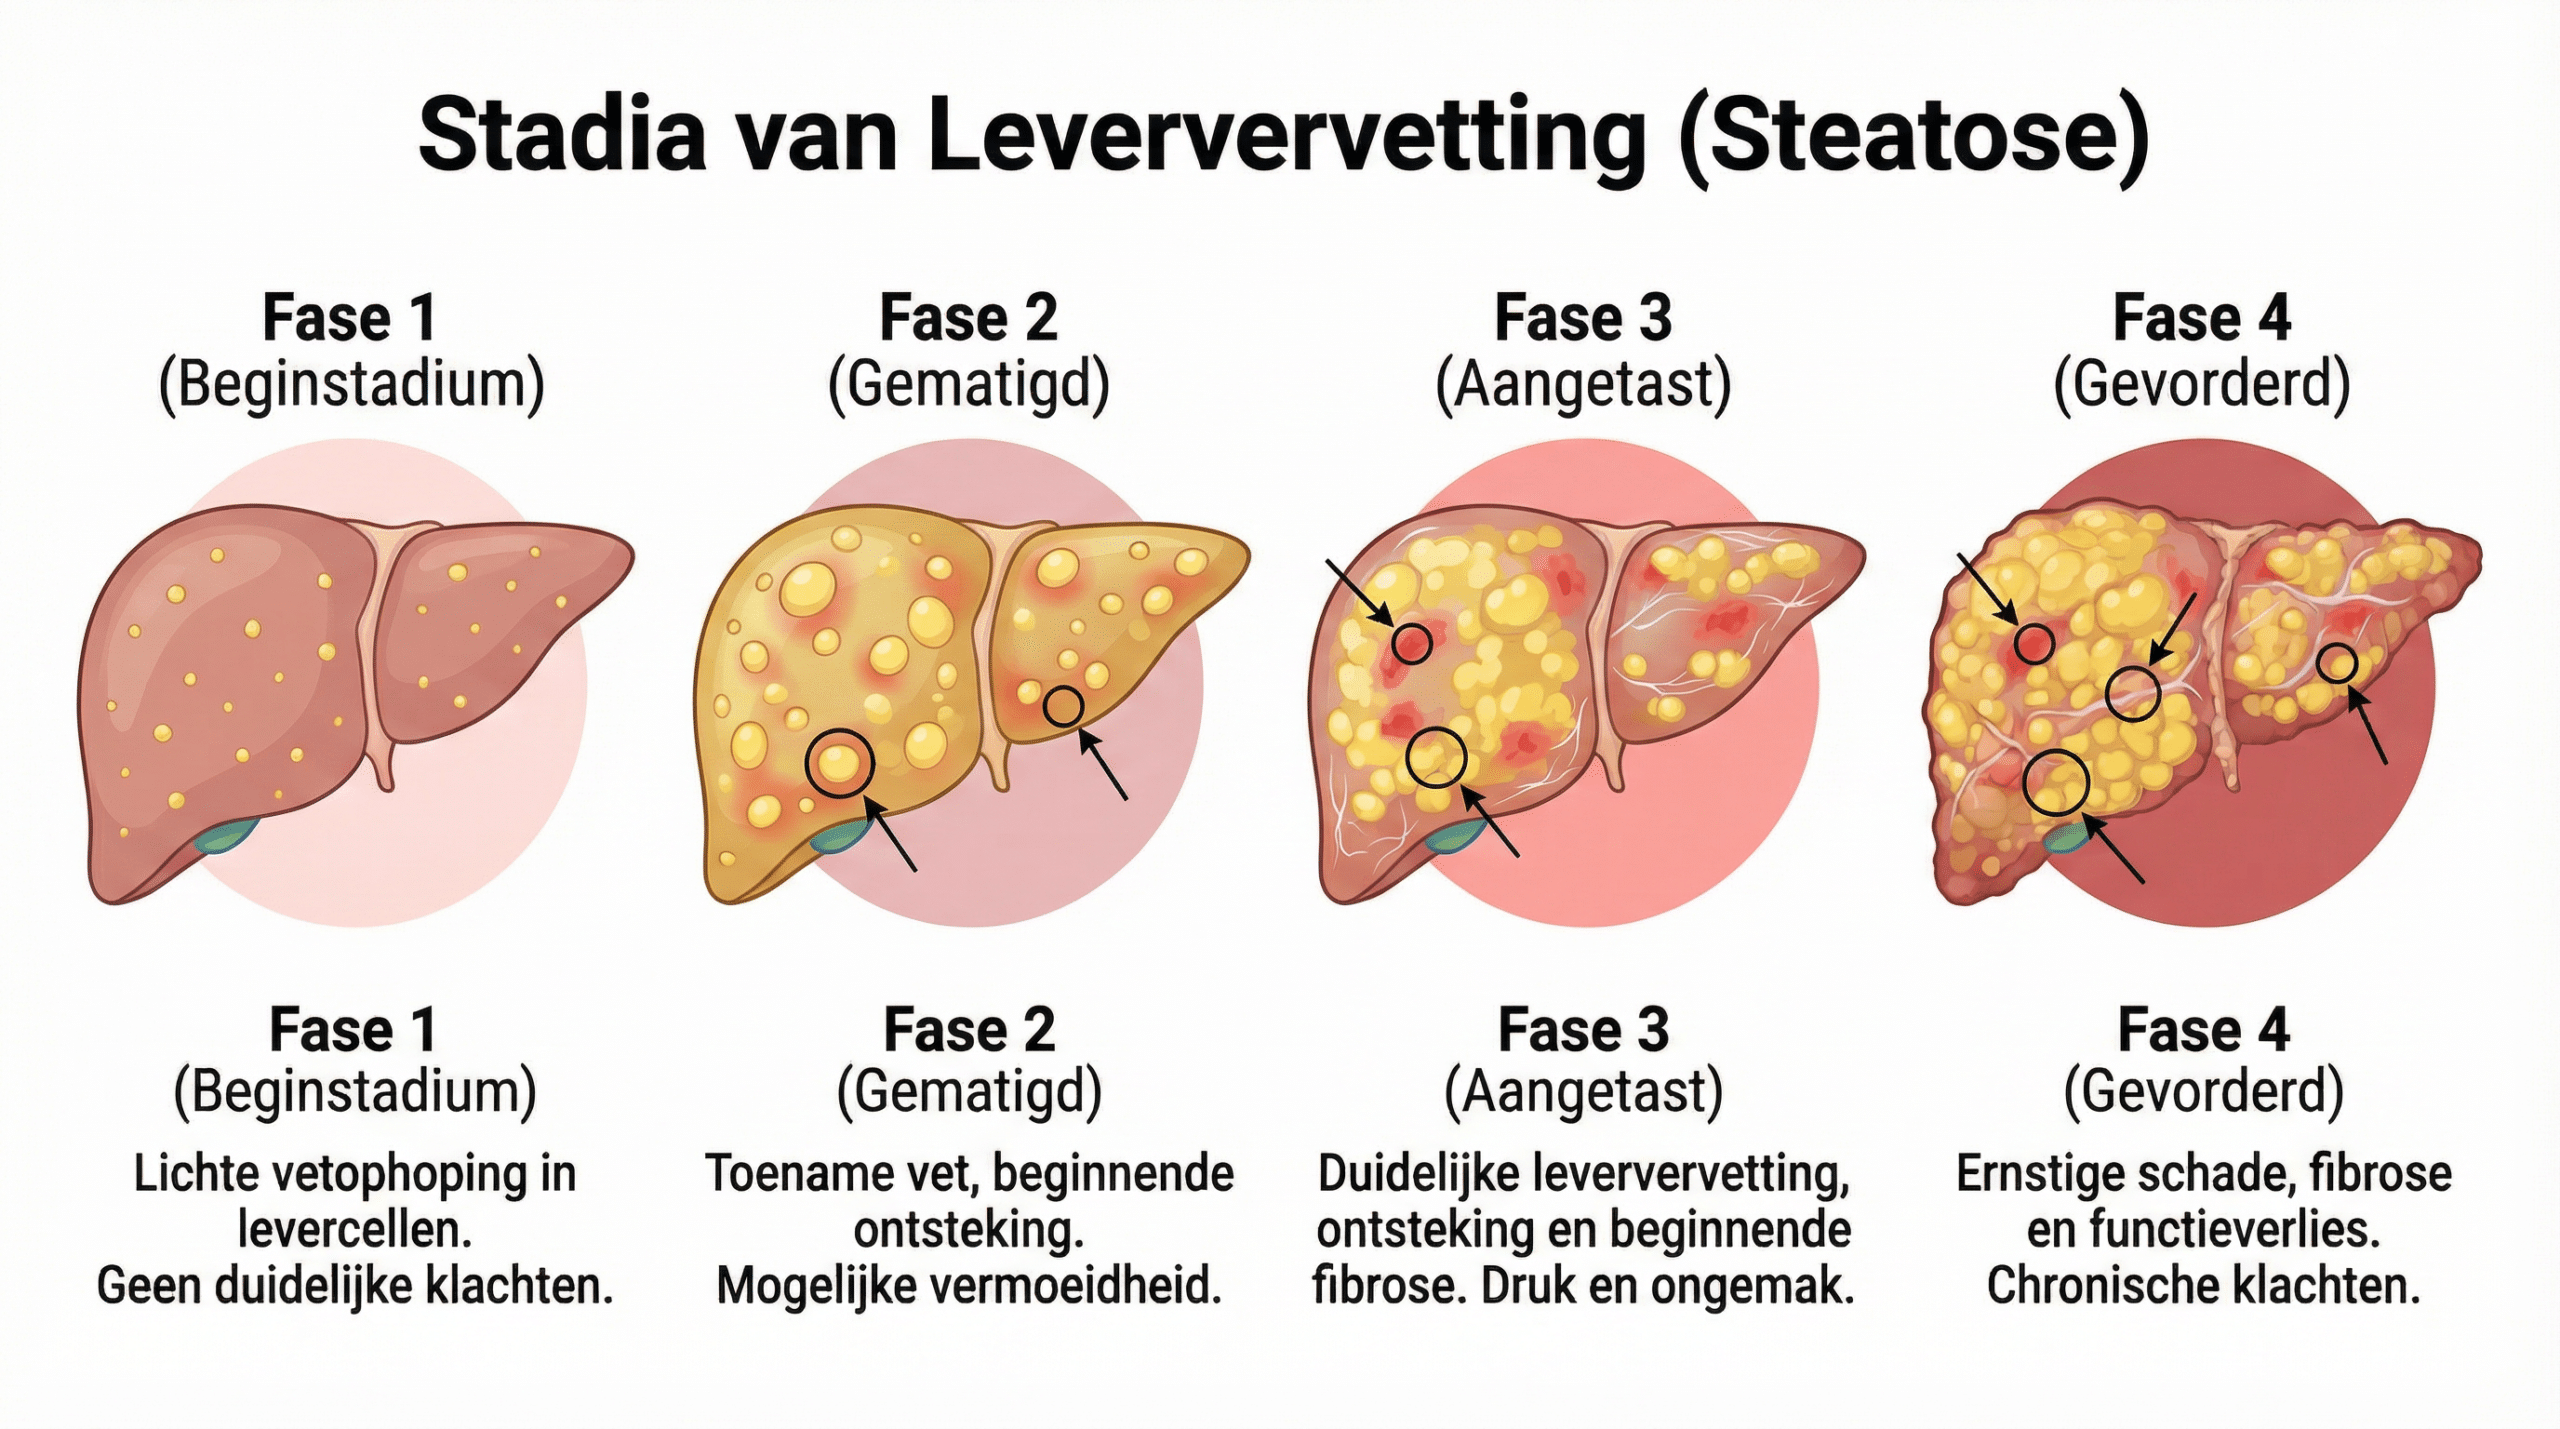

Als We De Vetopstapeling Niet Aanpakken, Wordt Het Alleen Maar Erger

Wanneer dit gebeurt, begint de lever verder te beschadigen en neemt de ontsteking toe — wat leidt tot steeds hogere druk op de levercellen.

Vetdruppeltjes groeien en beschadigen steeds meer cellen…

En zo beginnen de vermoeidheid, de verhoogde waarden en de lichamelijke klachten toe te nemen.

Elke ochtend wakker worden met een uitgeputte, zware vermoeidheid die geen nachtrust lijkt te verhelpen.

Met de tijd wordt het eerder erger dan beter.

Stel je voor: dag na dag, terwijl je lever steeds meer vetcellen opslaat in plaats van verbrandt, groeit de schade — totdat dingen die je vroeger vanzelfsprekend vond, zoals helder denken, energiek door de dag gaan of gewoon jezelf voelen, steeds verder wegglijden.